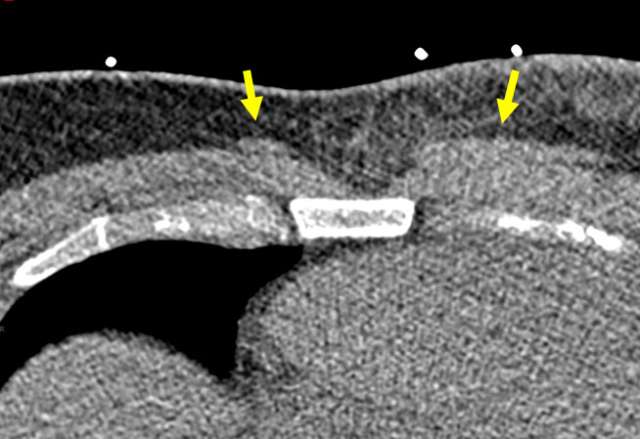

Magnetic Resonance Imaging and Computed Tomography Appearance

On MRI, the sternalis muscle demonstrates signal isointense to skeletal muscle. Likewise, CT scans depict the sternalis muscle as a well-demarcated structure with attenuation values similar to those of muscle, located anterior to the sternum. The shape is most often flat but can also be oblique or irregular (4). The presence of enhancing components on either MRI or CT is not typical and should prompt further evaluation or tissue sampling.